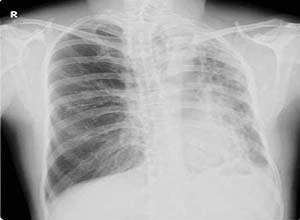

简介先天性肺发育不全,英文名为congenitalagenesisoflung ,别名Congenitalaplasiaoflung 。肺先天性发育不全可根据其发生程度分为3类:肺未发生(agenesis):一侧或双侧肺缺如;肺未发育(aplasia):支气管原基呈一终端盲囊,未见肺血管及肺实质;肺发育不全(hypoplasia):可见支气管、血管和肺泡组织但数量和(或)容积减少。患者可能伴发肺血管及其他畸形病变。

温馨提示:严重病例出生后即死亡。主要表现为呼吸困难,甚至呼吸窘迫,以及长期反复呼吸道感染,体检可见患侧胸廓塌陷,活动度减弱,叩诊呈浊音,听诊呼吸音减低或消失患者可伴有其他先天性畸形的临床表现。